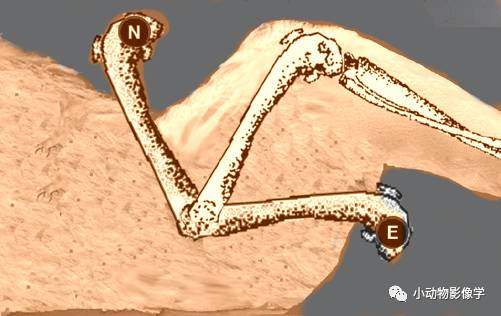

④半轴X光影像:双侧股骨平行且部分伸展,两股骨之间放置毛巾卷并用力下压,双侧跗部向中间加压,由于支撑物的作用关节可能会分离。

骨盆半轴照,E伸展,N正常

骨盆半轴照